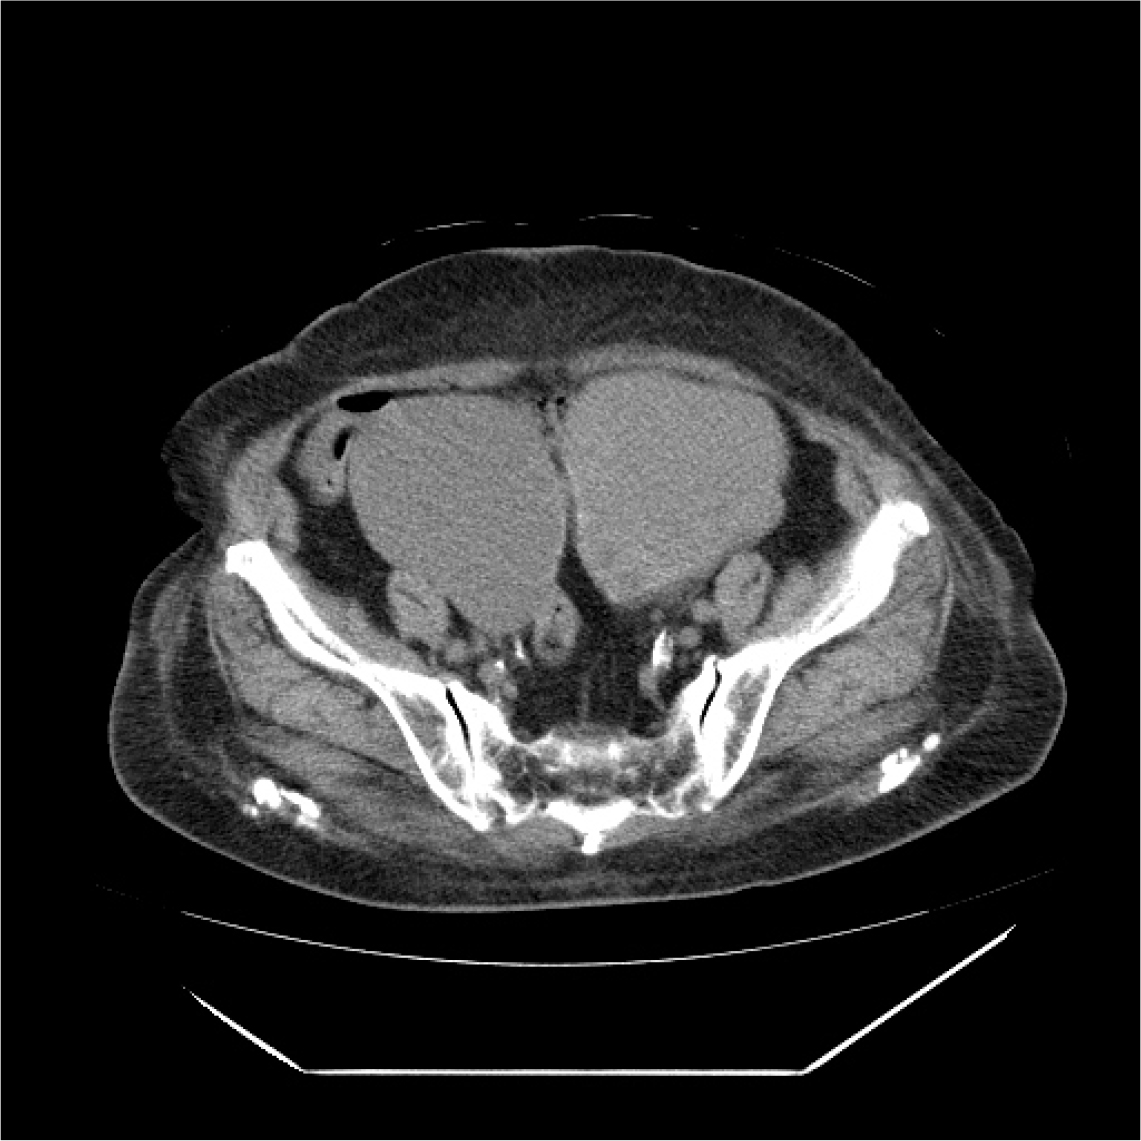

86세의 여성이 배뇨 곤란이 갑자기 심해져서 내원하였다. 환자는 20년 전 요실금 수술을 받은 병력이 있다. 3년 전부터 본원에서 야간뇨와 급박뇨를 치료받던 중 외래 추적 소실 후 3개월 만에 갑자기 발생한 배뇨 곤란 증세로 내원하였다. 신체 검사에서 하복부팽만 및 전신부종소견이 있었다. 초음파검사에서 왼쪽 난소 heterogenous density solid and cystic tumor, 오른쪽 난소에 large cystic tumor 소견이 관찰되었다. 골반 CT를 시행하였고 both ovaries malignancy Krukenberg tumors, 10 cm in each sides secondary stomach tumor 소견이 관찰되었다. 환자는 대학병원으로 전원되었으나 3개월후 사망하였다.